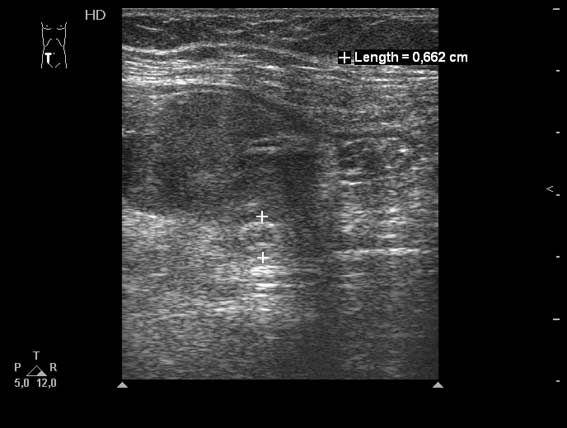

Женщина 59 лет поступила в приемное отделение БСМП с болями и пальпируемым образованием в правой подвздошной области.

О.аппендицит, аппендикулярный абсцесс. Задренирован, санирован, пациентка выписана домой.

На прошлой неделе появилась в клинике повторно для плановой аппендэктомии. При УЗИ патологии в правой подвздошой области не выявлено.